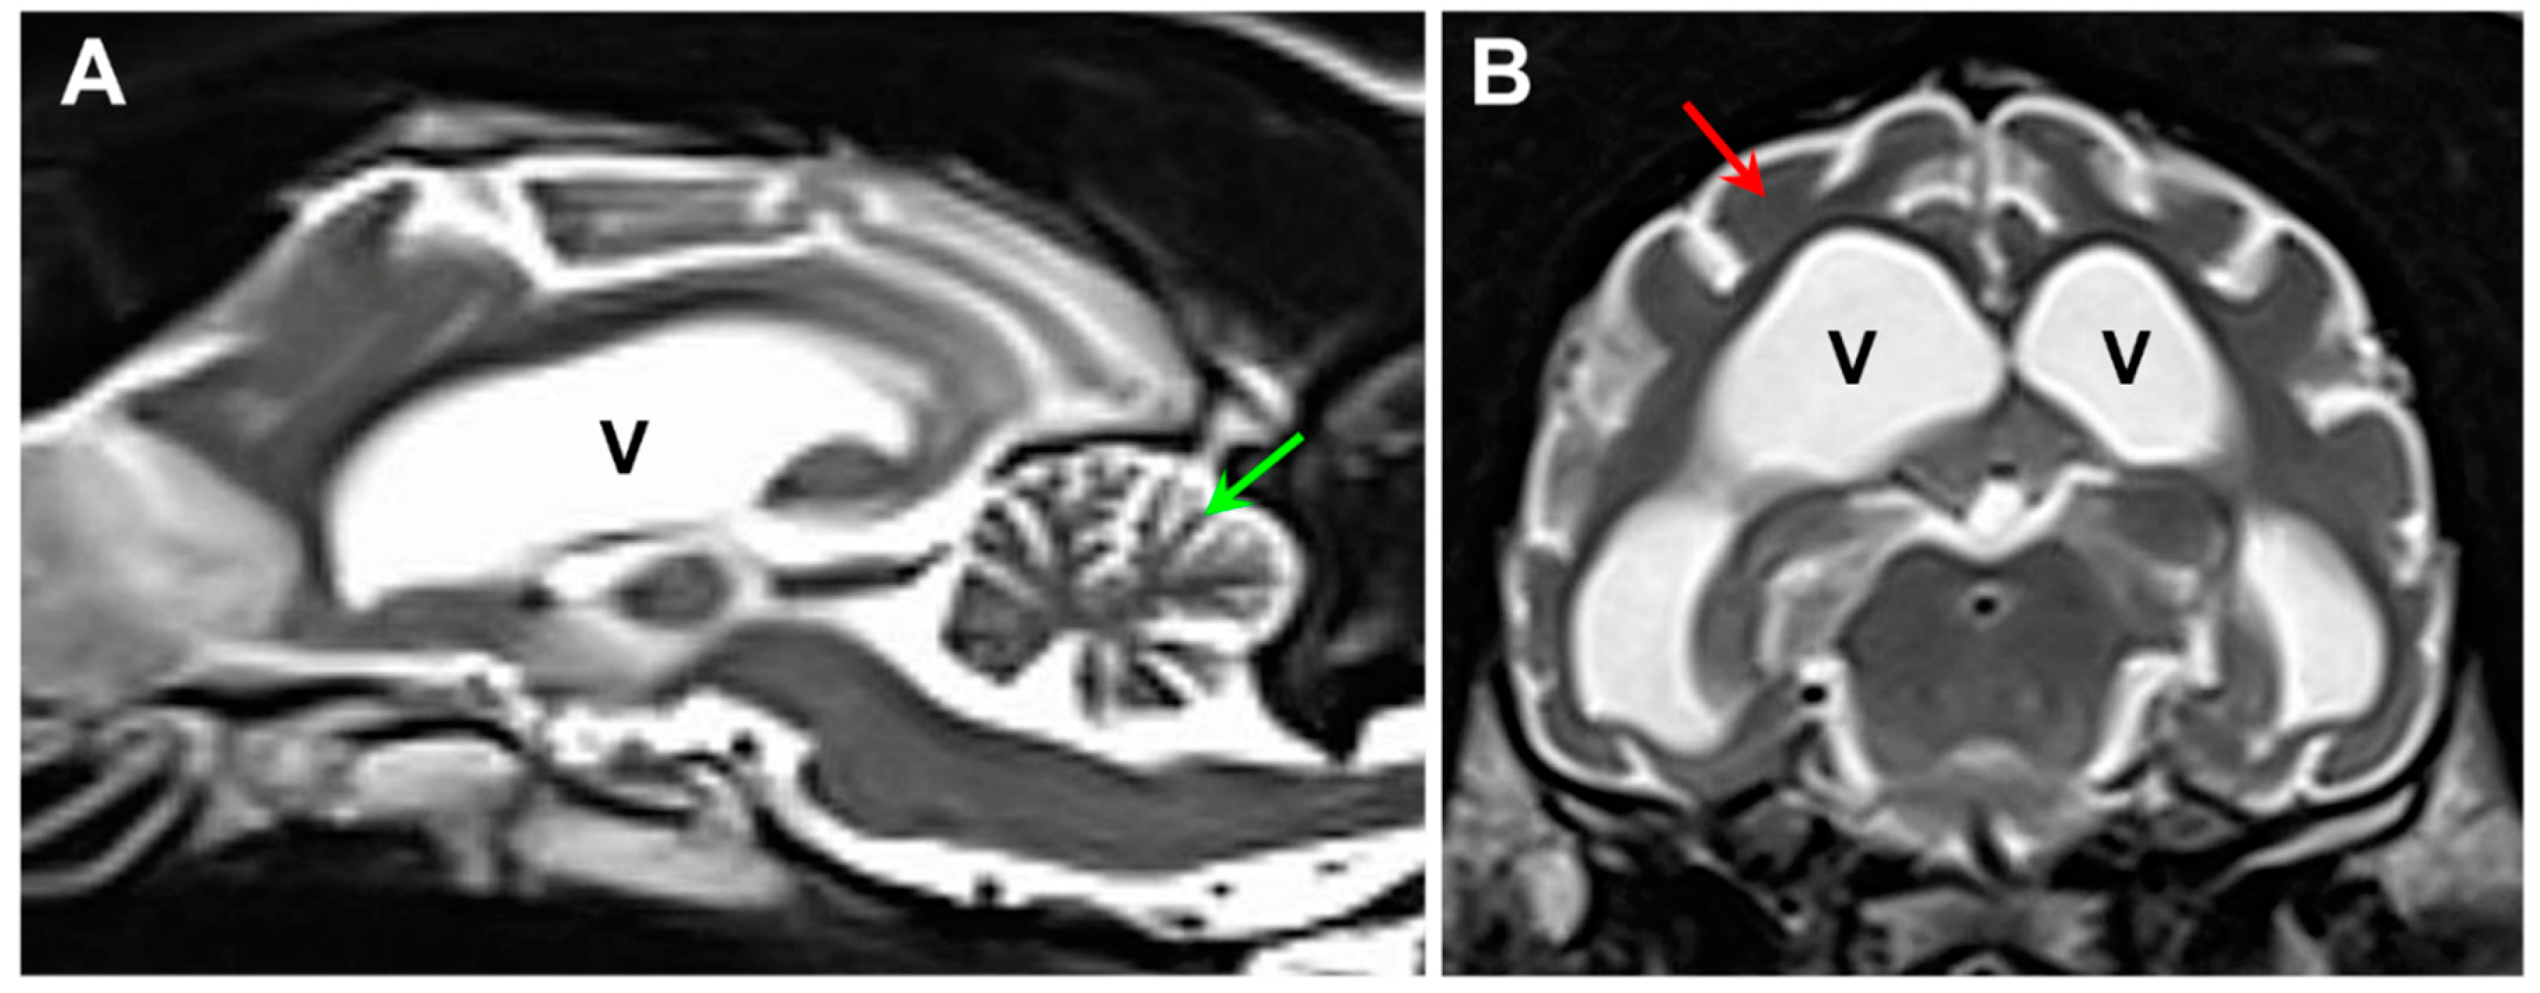

A 23-month-old neutered male dog of unknown ancestry (Figure 1) presented after a 4 month history of progressive neurological signs that included anxiety, cognitive impairment, tremors, seizure activity, ataxia, incoordination, and pronounced visual impairment. Marked diffuse brain atrophy was documented with magnetic resonance imaging (Figure 2). The dog was euthanized at approximately 26 months of age due to the progression of the neurological signs. Following euthanasia, the eyes, brain and heart ventricular wall were collected and preserved with aldehyde fixatives for light and electron microscopy, as described previously [8]. “Immuno Fix” consisting of 3.5% paraformaldehyde, 0.05% glutaraldehyde, 120 mM sodium cacodylate, and 1 mM calcium chloride, pH 7.4 was used for the light microscopy and immunohistochemistry samples. “EM Fix” consisting of 2% glutaraldehyde, 1.12% paraformaldehyde, and 120 mM sodium cacodylate, pH 7.4 was used for electron microscopy samples. Unstained cryostat sections of retina, cerebral cortex, cerebellar cortex, and cardiac muscle fixed for light microscopy were examined for lipofuscin-like autofluorescence [7]. Slices of the same tissues fixed in “Immuno Fix” were embedded in paraffin. Sections of the paraffin-embedded samples were immunostained using Abcam (Cambridge, UK) anti-mitochondrial ATP synthase subunit c primary antibody (cat. no. ab180149, dilution 1:100), Agilent Dako (Agilent Technologies, Santa Clara, CA, USA) anti-GFAP primary antibody (cat. no. Z0334, dilution 1:200), Fujifilm Wako (Fujifilm North America, Lousiville, KY, USA), anti-Iba1 primary antibody (cat. no. 019-19741, dilution 1:100), and Abcam anti-CLN6 antibody (cat. no. ab272678, dilution 1:50). Antigen retrieval and immunostaining was performed as described previously [7,9]. Paraffin sections of Immuno-fixed brain samples from a 12-month-old Shiba Inu that was euthanized due to seizures were also immunolabeled with the anti-CLN6 antibody. Pieces of the same tissues fixed in “EM Fix” were post-fixed with osmium tetroxide and embedded in epoxy resin. Thin sections of the latter samples were examined with transmission electron microscopy using a JEOL JEM-1400 microscope equipped with a Gatan digital camera.

Figure 2. Sagittal (A) and axial (B) T2-weighted MR images of the proband’s brain. The ventricular system (V) was dramatically enlarged, and there was a pronounced shrinkage of the parenchyma of both the cerebellum (green arrow in A) and the cerebral cortex (red arrow in B).